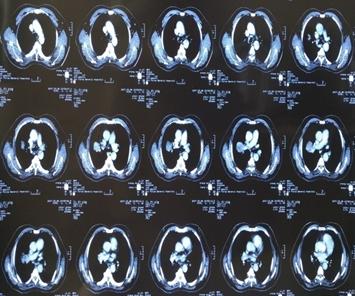

患者刘某某,男,65岁, 13年前因咳嗽、咳痰带血半年就诊,胸部CT示右上肺占位,支气管镜示右上叶前段支气管远端狭窄,活检病理:中低分化鳞癌。诊断:右上肺中低分化鳞癌,T4N1M0,IIIB期。

因二次全麻下气管插管出现哮喘无法手术,于2007年5月30至2007年6月28日进行局部放射治疗,同时给予对症支持治疗。照射剂量PTV(肿瘤外5mm)66GY/22f/30d;GTV(肿瘤边缘)70GY/22f/30d;GTV1(肿瘤内部)77GY/22f/30d;治疗期间,咳嗽缓解、无咯血,血常规 基本正常 范围,按计划完成治疗。

治疗后5年复查,患者偶有咳血,局部病灶纤维化改变

治疗后11年复查,无明显活动后 气喘 。